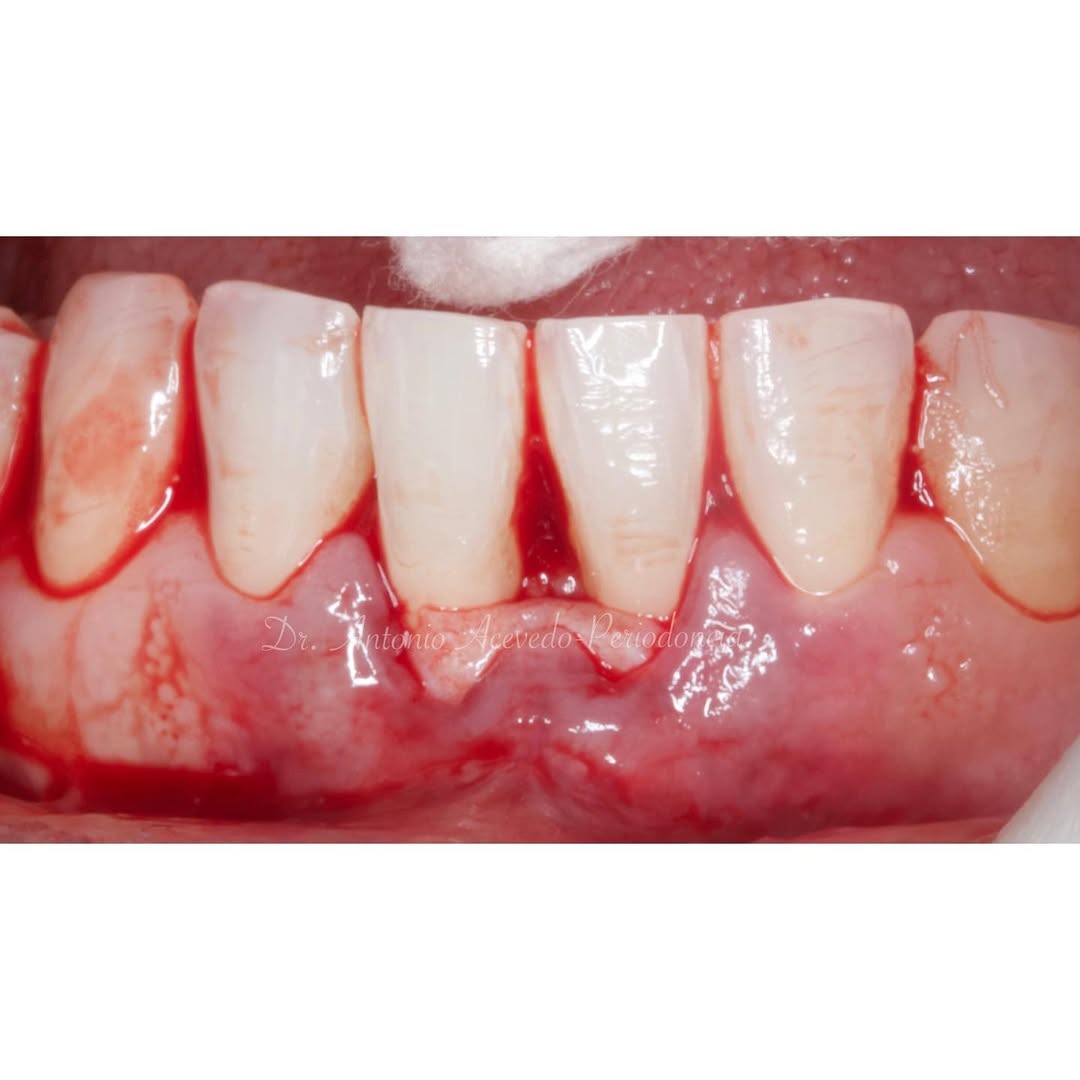

Durante una mañana, asistirás a una Cirugía Mucogingival de recubrimiento radicular de recesiones múltiples en IV y V sextante (36 a 43).

Gracias al uso del microscopio y a la proyección en tiempo real en pantalla, verás exactamente lo mismo que veo yo durante la cirugía, sin tener que estar

Aprende la planificación y técnica de la cirugía Mucogingival para el recubrimiento de recesiones y aumento de banda queratinizada en el sector anteroinferior